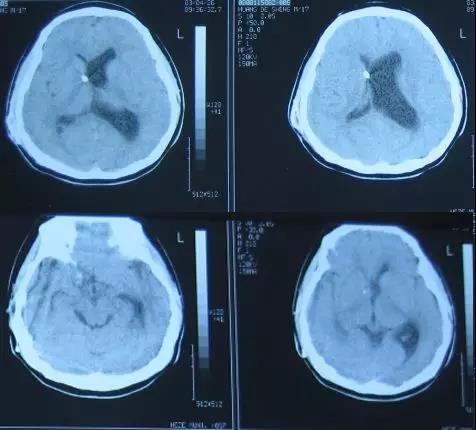

出院后8年即2011年7月22日即患者23岁时,患者出现情感淡漠,表情冷漠,再次就诊于山东省菏泽市某医院,复查头部CT示脑室稍有扩张(图-2),未给予特殊处理。

图-2:2011年7月22日头部CT

又经过一个月即2011年8月17日,患者出现语言及行动迟缓病情加重的症状,遂就诊于山东省济南市某三甲医院,头部MRI示脑积水(图-3)。

图-3:2011年8月17日头部MRI